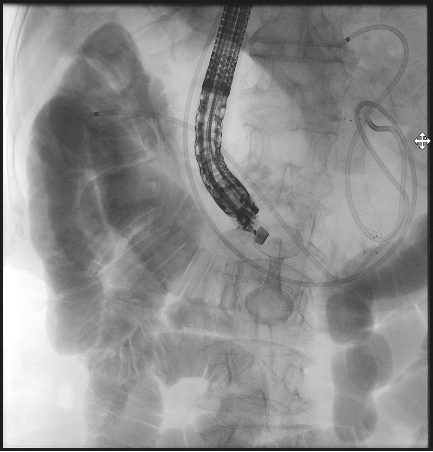

手术室中,一场没有体表切口的“体内造桥工程”悄然开启。

超声内镜探头如同高精度的“GPS导航”,在胃腔内实时扫描,清晰显示出肿瘤的边界、周围血管的搏动,以及最佳“桥墩”定位点。

在超声的实时引导和X光造影的监控下,穿刺、导丝置入、支架释放……

一系列步骤如行云流水。

当那枚双蘑菇头支架在胃与空肠之间成功展开,宛如一朵生命之花在体内绽放,一座避开所有险滩的“人工桥梁”就此贯通。